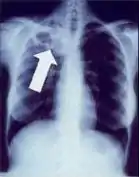

1. Infiltrate or consolidation - Opacification of airspaces within the lung parenchyma. Consolidation or infiltrate can be dense or patchy and might have irregular, ill-defined, or hazy borders.

Dense homogenous opacity in right, middle and lower lobe of primary pulmonary TB.